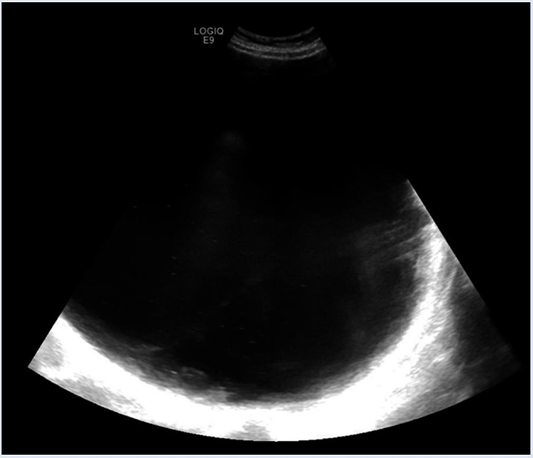

On examination, the patient appeared to be obese, welldeveloped, anxious, and cooperative. She was not able to tolerate a speculum examination due to the pain. There was no pulsatile abdominal mass, guarding of the abdomen, nor any generalized and/or rebound tenderness or rigidity. The lower left quadrant of the patient’s abdomen was tender with mild distention and normal bowel sounds were heard. An elevated blood pressure on admission (145/89) was noted. The urinalysis was unremarkable. Blood analysis showed hypochromic, microcytic anemia (10.3 g/ dL) with +1 anisocytosis (generally associated with iron deficiency anemia [11], and mild elevated chloride (109 mEq/L) and elevated glucose (109 mg/dL) levels. A pelvic ultrasound reported a normal uterus with no endometrial abnormalities, and the right ovary appeared normal. The left ovary was not visualized (Figures 1 and Figure 2). A large cystic structure was seen, whose origin was unknown. An abdominal/pelvic computerized tomography (CT) with contrast found a 36 cm cyst lesion filling the abdominal and pelvic cavity which appeared to originate from the left adnexa with a complicated hyperdense fluid or debris focus noted in the inferior margin of the cyst (Figure 3). The surrounding structures appeared unremarkable. There was a trace amount of fluid in the Pouch of Douglas. (Figure 4).

Figure 1: Image of the cyst on transabdominal ultrasound. Due to the size of the cyst, it could not be visualized entirely within the same image.